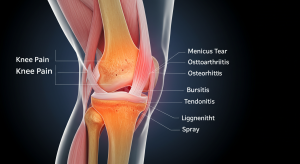

The knee is one of the most complex and largest joints in the body, connecting bones, ligaments, and muscles. Poor habits such as prolonged sitting, lack of exercise, or carrying excess weight place stress on the knees, leading to pain and inflammation. Consistent care through healthy choices helps prevent conditions like arthritis, meniscus tears, and chronic joint stiffness.